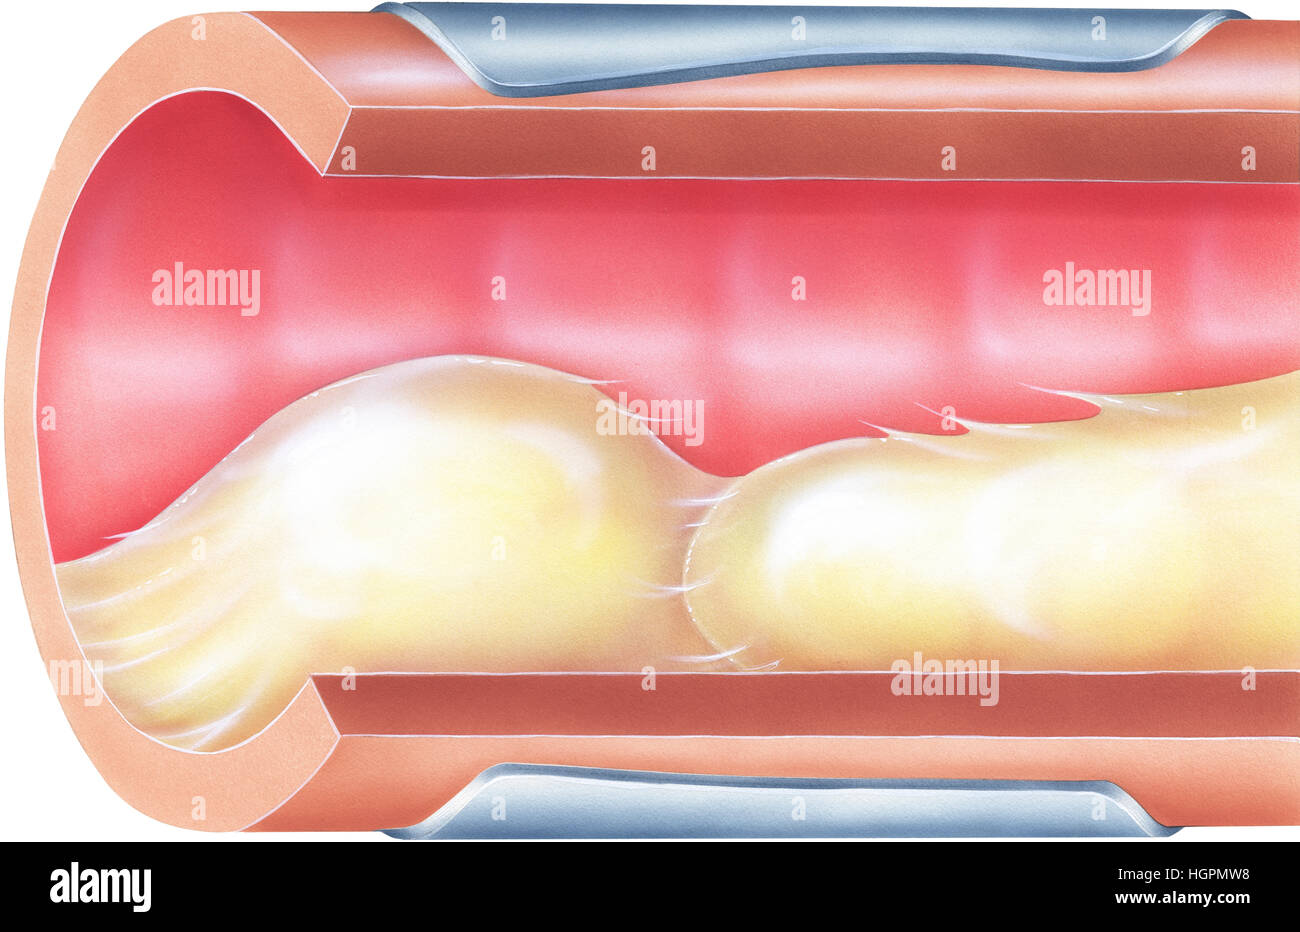

Lungs - Bronchial Mucus. Shown is bronchial airway obstruction and narrowing due to viscid mucus. Stock Photohttps://www.alamy.com/image-license-details/?v=1https://www.alamy.com/stock-photo-lungs-bronchial-mucus-shown-is-bronchial-airway-obstruction-and-narrowing-130806404.html

Lungs - Bronchial Mucus. Shown is bronchial airway obstruction and narrowing due to viscid mucus. Stock Photohttps://www.alamy.com/image-license-details/?v=1https://www.alamy.com/stock-photo-lungs-bronchial-mucus-shown-is-bronchial-airway-obstruction-and-narrowing-130806404.htmlRFHGPMW8–Lungs - Bronchial Mucus. Shown is bronchial airway obstruction and narrowing due to viscid mucus.

Shown is bronchial airway obstruction and narrowing due to viscid mucus. Excessive mucus in bronchial airways can cause significant obstruction and an Stock Photohttps://www.alamy.com/image-license-details/?v=1https://www.alamy.com/stock-photo-shown-is-bronchial-airway-obstruction-and-narrowing-due-to-viscid-130806403.html

Shown is bronchial airway obstruction and narrowing due to viscid mucus. Excessive mucus in bronchial airways can cause significant obstruction and an Stock Photohttps://www.alamy.com/image-license-details/?v=1https://www.alamy.com/stock-photo-shown-is-bronchial-airway-obstruction-and-narrowing-due-to-viscid-130806403.htmlRFHGPMW7–Shown is bronchial airway obstruction and narrowing due to viscid mucus. Excessive mucus in bronchial airways can cause significant obstruction and an